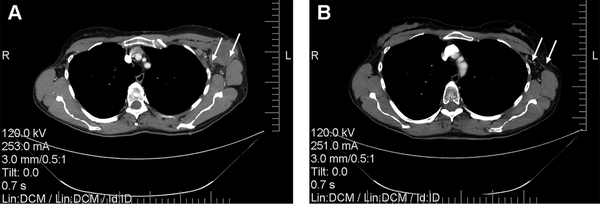

There were no significant differences in the size of regional lymph nodes between the 2 groups prior to any treatment procedures. The combination of NACT and RIMH showed a decrease of 7.67 mm (32.08 ± 4.13)% in the size of the involved lymph nodes, whereas BC patients given NACT alone had a 5.79 mm (17.91 ± 4.35)% reduction on average. Figure 6 presents a typical case of the lymph node reduction in a BC patient treated with NACT + RIMH. There was a 14.17% difference in the treatment response of axillary lymph node metastasis between NACT followed by RIMH and NACT alone (p = 0.011).

Figure 6

Computed tomography scans of the chest showing reduction of axillary lymph node metastasis in a 47-year-old patient who received NACT combined with RIMH: A—before combined treatment; B—after combined treatment. White arrows indicate axillary lymph node metastasis. Abbreviation: NACT, Neoadjuvant chemotherapy; RIMH, Regional inductive moderate hyperthermia.